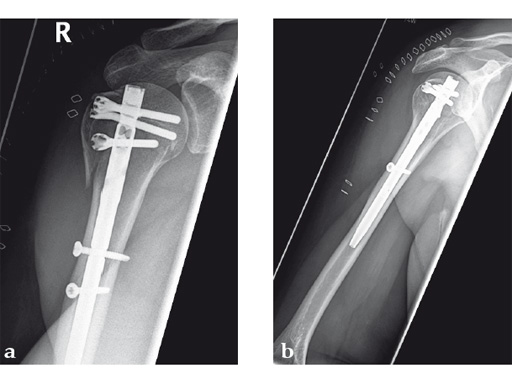

Following a fall downstairs, a 70-year-old woman sustained a head injury with intracerebral and subdural haematoma, as well as a complex fracture of the right humerus, representing a minimal displaced proximal and an oblique fracture in the distal part of the humerus (Fig 11).

After neurosurgical intervention, surgery of the humerus was planned 10 days after the index trauma. The patient was still at the neurological intensive care unit and a preoperative clinical examination of the patient, regarding radial nerve palsy, was not possible. Therefore, a surgical revision with exploration of the radial nerve and an osteosythesis of the humerus using a long MultiLoc Humeral Nail was indicated.

The patient was operated on in beach chair position. For the exploration of the radial nerve, a limited anterolateral approach was used. The nerve was mobilized and retracted laterally. An anterolateral approach to the proximal humerus was performed. The supraspinatus showed a small acute rupture without retraction. The supraspinatus tendon was split to get access to the insertion area on the humeral head. A 270 mm long MultiLoc Humeral Nail of 8.5 mm diameter was inserted under visual and x-ray control to the desired endpoint. Reduction of both the proximal and the distal humerus fracture was anatomical. In the lateral view there was a small gap, and it was decided to apply compression after distal locking (Fig 12). Proximally, three MultiLoc screws were inserted and a 2 mm end cap was placed. Finally, the supraspinatus rupture was reconstructed with transosseous sutures and secured with an augmentation plate. The posterior greater tuberosity fracture was secured with Fiber Wire to the MultiLoc screws. Fig 13 illustrates the definitive fixation.